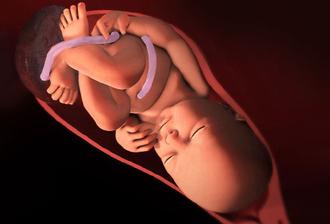

29.4. druhá KO u dr 7+3, 12,3mm a srdíčko bije

23.5. pro průkazku + odběr krve + utz 11+0 mimisek 4,2cm